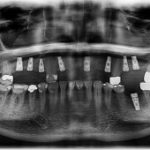

This patient had been unhappy with her loose lower denture.  Placed four Implants to secure lower denture and she is now happy to report back that she can eat steak!

This patient had only a few remaining infected teeth, but didn’t want to settle for just a denture.  Placed multiple implants and provided a secure fixed option which allowed him to not only chew better but to smile again.